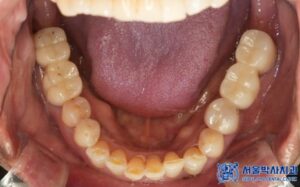

임플란트 수술이 끝나고 임플란트가 잘 고정된 후에는,

저희 서울박사치과 원내기공소에서 제작한

개인 맞춤형 보철물을 세팅해드렸습니다.

저희 기공소에는 10년 이상의 경력을 지닌

전문 치과기공사가 상주하여,

단순히 예쁜 보철물만이 아닌 퀄리티가 높은

기능적이고 편안한 보철을 제작해 드리고 있습니다.

특히 맞춤형 지대주를 제작하여 음식물 끼임을

줄이고 환자 개개인의 구강구조에 꼭 맞게

보철물을 제작합니다.

또한 고품질 재료를 사용해 내구성이 뛰어나고

심미성이 우수하며,

보철물이 어색하거나 불편하실 경우에도 원내에서

빠르게 조정해드릴 수 있는 것이 큰 장점입니다.

치료 마무리 후 사진입니다.

최종 보철물 세팅 이후 환자분께서는 불편함도 없었고,

교합 체크를 위해 다시 내원하셨을 때도

“음식 씹을 때 너무 편하고, 교합도 잘 맞는다”고

만족해하셨습니다.